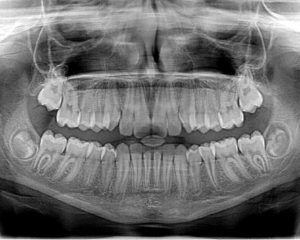

Aus unserer Gesundheitsecke